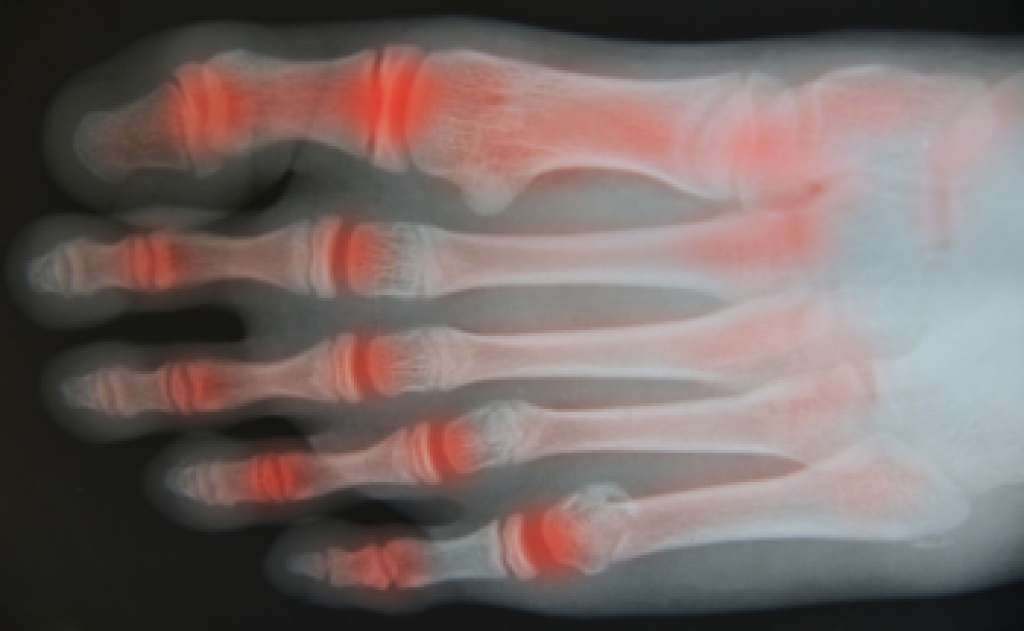

Foot pain is a common complaint among seniors, affecting approximately 20 percent of older adults regularly. Among the most common causes of foot pain in seniors are stress fractures, heel pain, diabetic neuropathy, gout, and blood clots. Seniors are more susceptible to stress fractures due to age-related changes in bone density. Stress fractures are tiny cracks in bones that typically manifest as pain during activity, but subside with rest. Plantar fasciitis, characterized by irritation and inflammation of the plantar fascia ligament on the sole of the foot, can cause persistent heel pain. Diabetes frequently leads to neuropathy, which causes tingling, burning, or numbness in the feet. Regular foot monitoring and care are essential for individuals with diabetes to prevent complications. A podiatrist can help manage conditions such as corns, calluses, and nail care. Gout, a form of inflammatory arthritis, typically affects the big toe. Sudden and severe pain, especially at night, may indicate gout. Blood tests or joint fluid analysis can confirm the diagnosis. Deep vein thrombosis, or a blood clot, is often associated with leg swelling and pain, but it can also cause sudden and severe pain in the ankle or foot. Seniors, especially those who smoke, are overweight, or are sedentary, may be at a higher risk. If you are experiencing foot or ankle pain that persists or worsens, it is suggested that you make an appointment with a podiatrist for treatment options.

- Neuropathy – can reduce feeling in the feet and can hide many life-threatening medical conditions.

- Loss of circulation in legs & feet

Diabetes and poor circulation can cause general loss of sensitivity over the years, turning a simple cut into a serious issue.